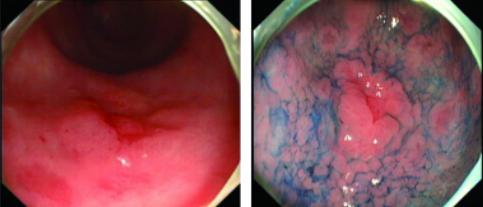

管状腺瘤伴低级别上皮内瘤变A:白光下B:NBI C:醋酸染色D:醋酸染色后NBI观察

绒毛状腺瘤伴高级别上皮内瘤变:A:白光下B:NBI C:醋酸染色D:醋酸染色后NBI观察